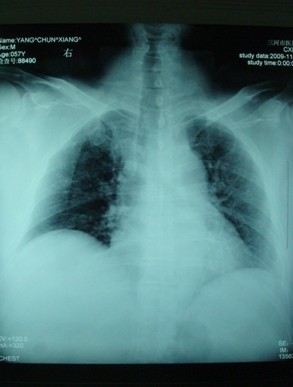

患者,男性,56岁, 因车祸伤致腰痛、胸痛、骨盆痛6小时来我院就诊。患者2009-11-8被汽车撞伤腰部,当时双下肢不能活动,伴头晕、大汗,无明显外出血,就诊于当地医院,查血压70/50mmHg,诊断为“多发伤,休克”,予抗休克治疗,X线和CT检查示“胸12椎体爆裂骨折、腰2-4右侧横突骨折(见图1、图2);右肩胛骨骨折(见图3、图4);多发肋骨骨折、右侧血胸(见图5);右耻骨上下支粉碎性骨折、右髂骨骨折合并右骶髂关节半脱位(见图6、图7)”。

图5 X线片提示多发肋骨骨折、右侧血胸